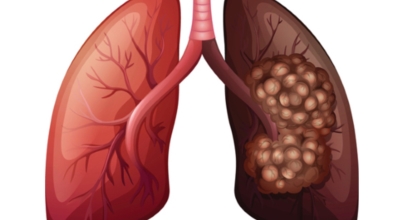

폐에 발생된 악성 종양을 말하며 오랜 기간 흡연해온 남성들에서 발병률이 높고 요즈음 각종 환경적인 요인의 영향과 간접흡연으로 흡연하지 않는 여성에서도 많이 발생하고 있습니다. 증상을 느껴 병원을 찾았을 때는 수술하기 늦은 경우가 많아 사망 가능성이 매우 높은 암입니다. 폐 자체에서 발생하거나 다른 장기에서 발생된 암이 폐로 전이되어 발생하기도 하고 특별한 초기 증상이 없는 경우가 많고 암이 진행된 후에도 공통적인 감기 증상인 기침과 가래 외의 특이 증상이 나타나지않아 증상만으로는 진단이 쉽지 않습니다.

폐암 역시 다른 암들과 마찬가지로 조기 발견 및 치료가 매우 중요하므로 일상 속에서 폐암 초기증상을 간과하지 않도록 주의를 기울여야 합니다. 따라서 장기간의 흡연, 간접흡연에 노출됐거나 일반적인 때 폐 기능이 좋지 않고 호흡기 질환에 잘 걸리는 예민한 편이라면 폐암 증상에 대하여 잘 알아뒀다가 이상이 있다고 생각되면 최대한 빨리 전문의를 찾아 정확한 검진을 받아보는 것이 좋습니다.